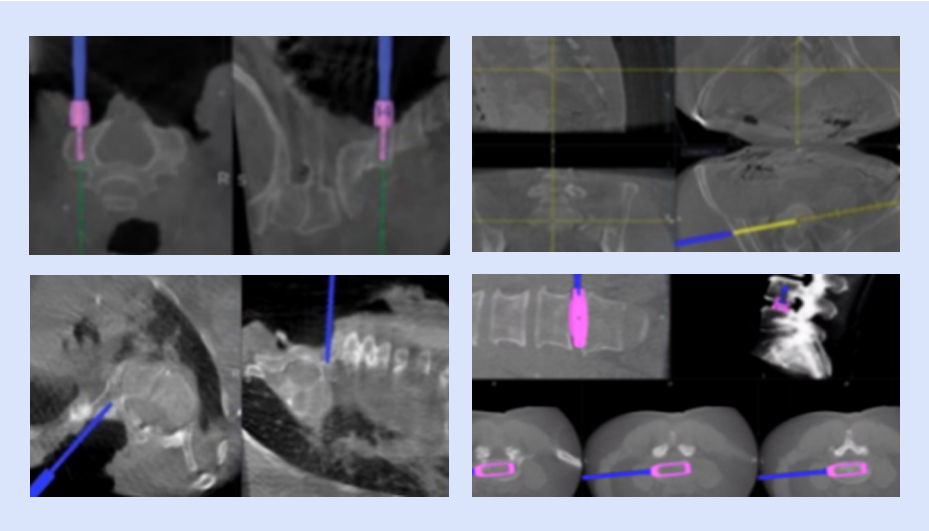

可視化置釘

確保導(dǎo)航設(shè)備正常運(yùn)行,檢查定位系統(tǒng)、手術(shù)器械、置釘系統(tǒng)等是否完好,以及設(shè)備是否處于最佳工作狀態(tài)